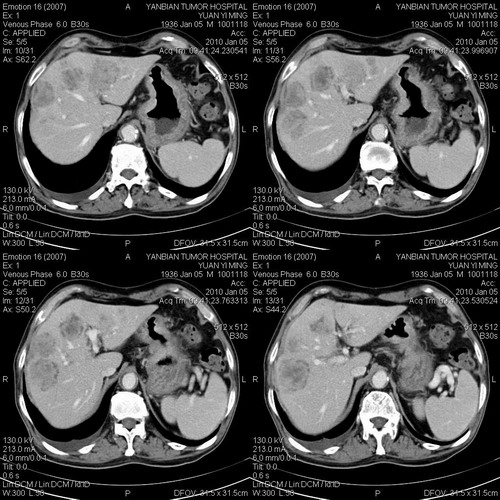

标题: CT24024:男,74岁。体检超声发现肝内多发占位性病变四天。 [打印本页]

标题: CT24024:男,74岁。体检超声发现肝内多发占位性病变四天。

肝癌肝内转移,胃壁增厚,胃癌不能排除

建议查afp。考虑多发结节型肝癌。

考虑多发结节性肝癌。

1)考虑肝脏恶性肿瘤(转移瘤?)。2)肝外胆管轻度扩张。3)左肾小囊肿。